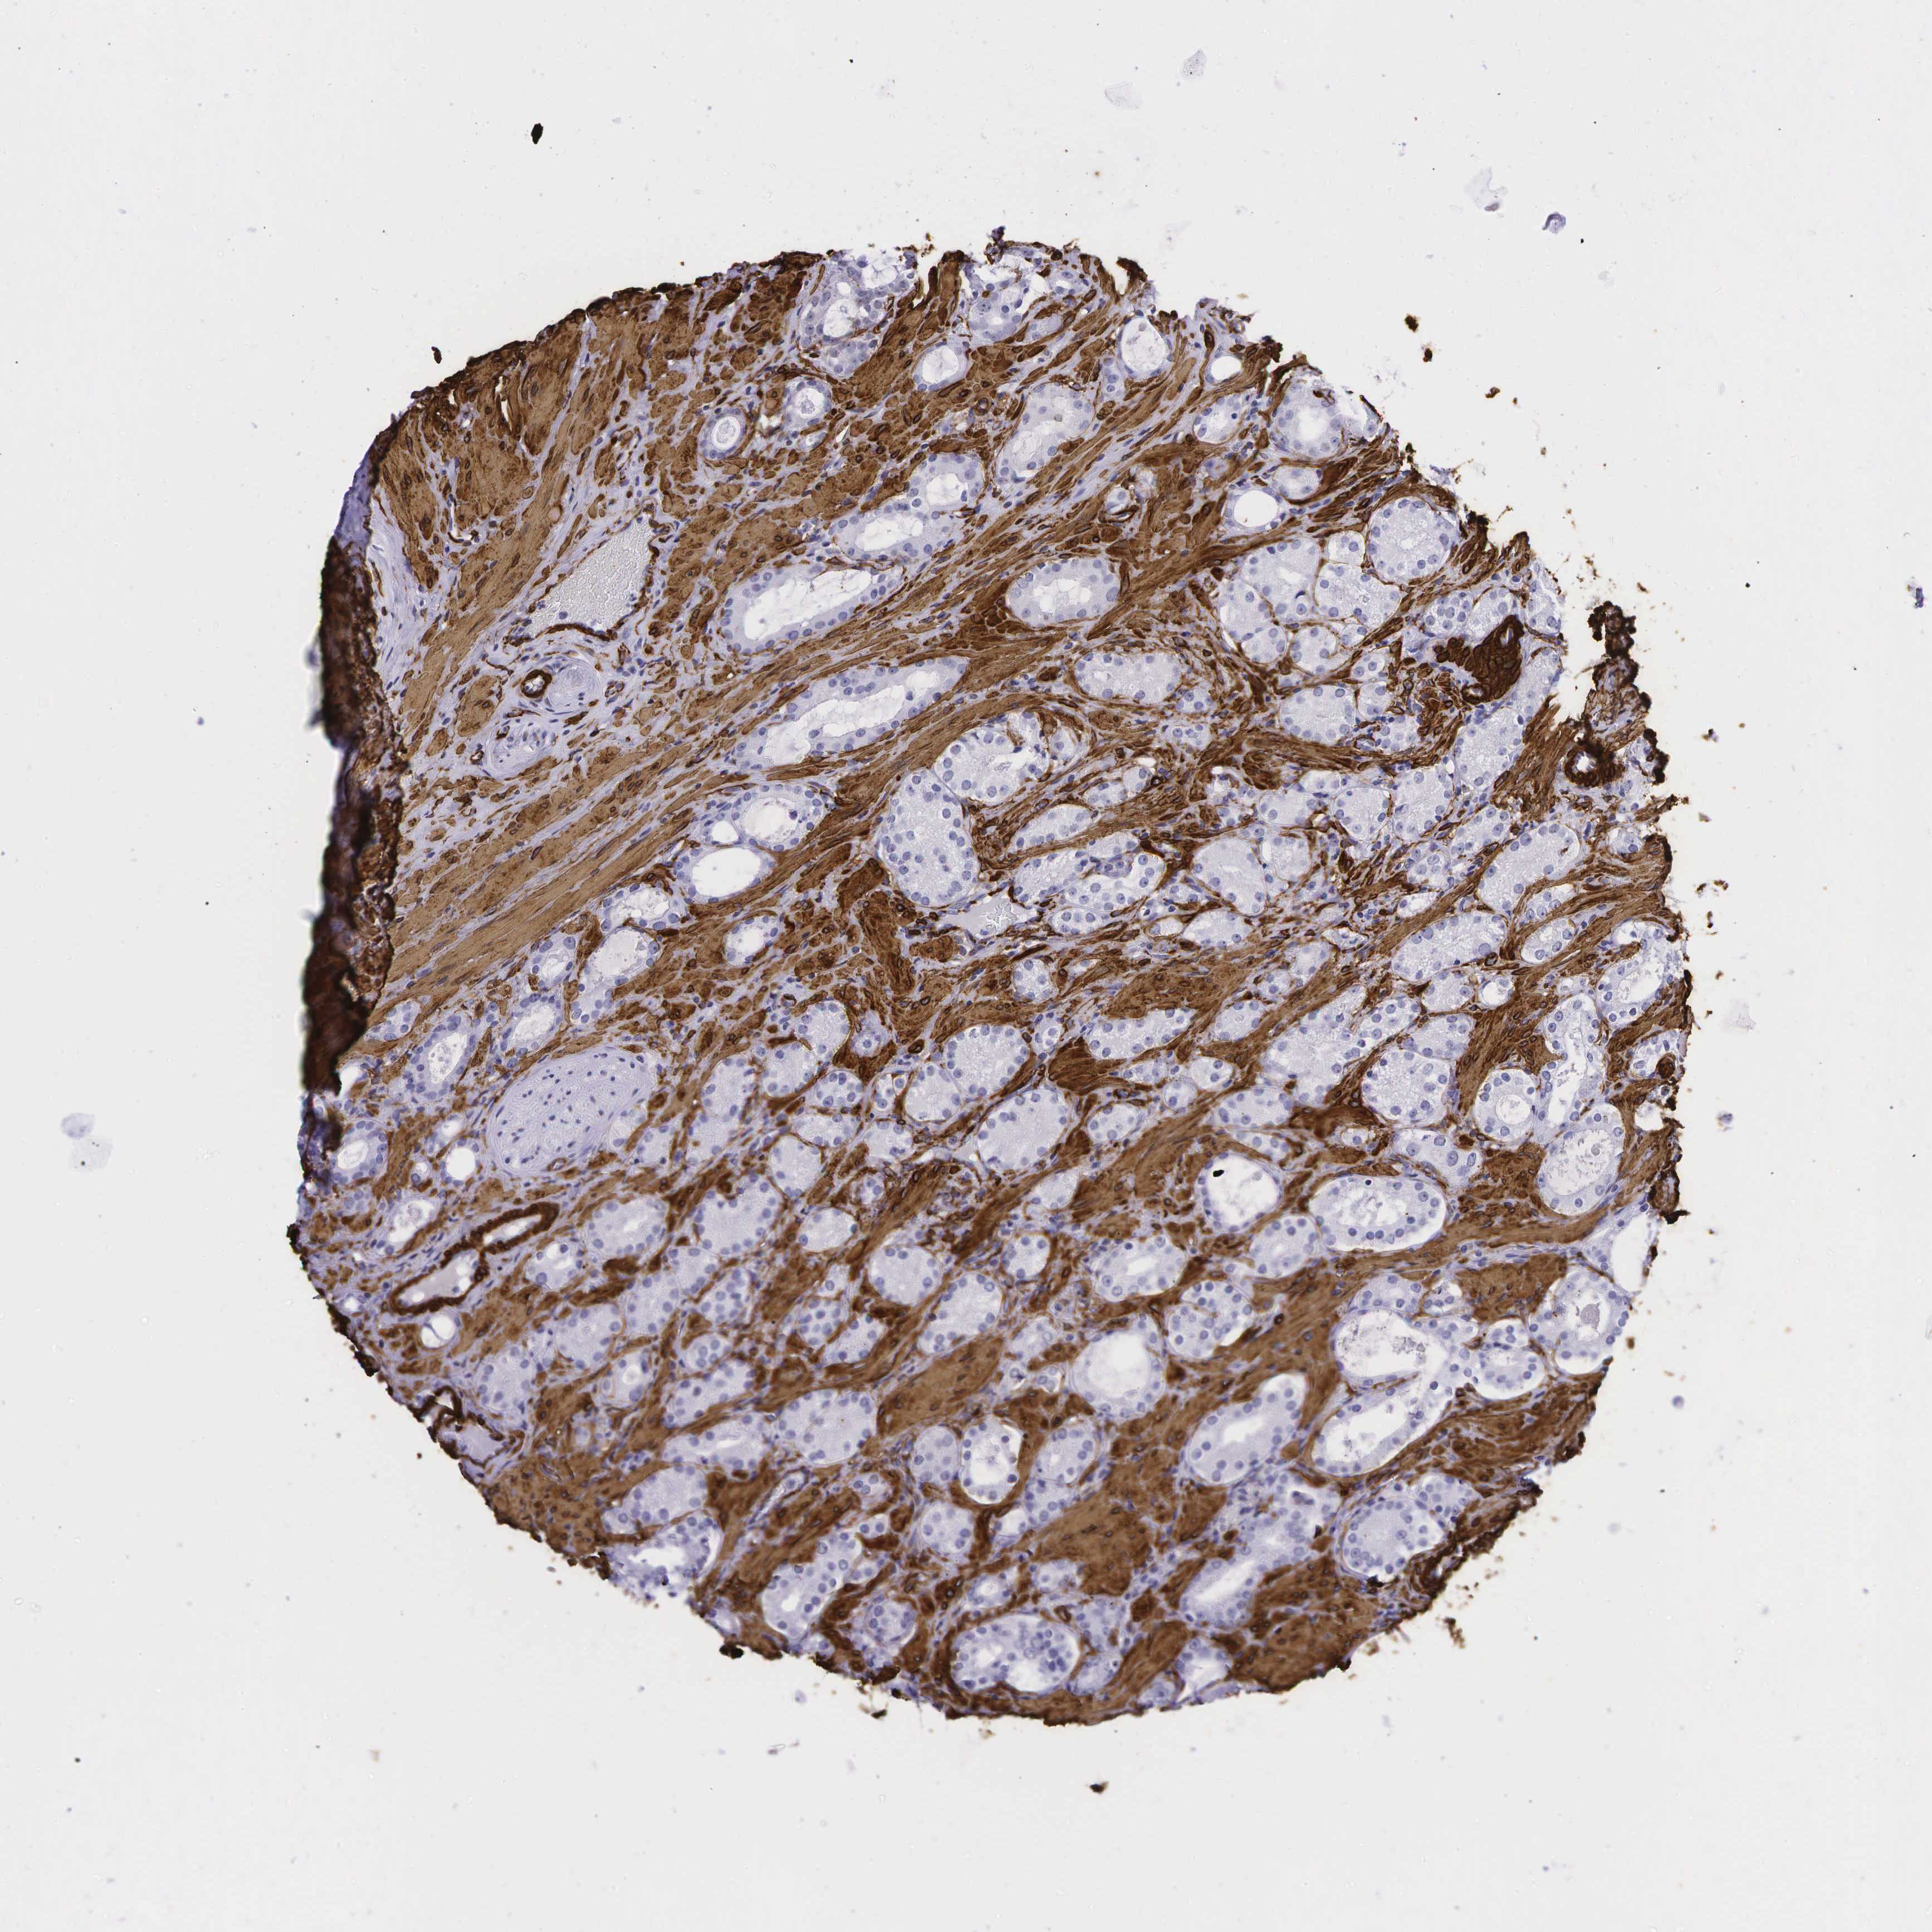

PROSTATE CANCER - Protein expressioni

A mouse-over function shows sample information and annotation data. Click on an image to view it in a full screen mode. Samples can be filtered based on level of antibody staining by selecting one or several of the following categories: high, medium, low and not detected. The assay and annotation is described here.

Note that samples used for immunohistochemistry by the Human Protein Atlas do not correspond to samples in the TCGA dataset.

Antibody stainingi

Antibody staining in the annotated cell types in the current human tissue is reported as not detected, low, medium, or high, based on conventional immunohistochemistry profiling in selected tissues. This score is based on the combination of the staining intensity and fraction of stained cells.

Each image is clickable and will lead to virtual microscopy that enables deeper exploration of all samples and also displays staining intensity scores, fraction scores and subcellular localization as well as patient and tissue information for each sample.

HPA041264

HPA041271

CAB000002

CAB003761

CAB013531

Staining

High

Medium

Low

Not detected

Intensity

Strong

Moderate

Weak

Negative

Quantity

>75%

75%-25%

<25%

None

Location

Nuclear

Cytoplasmic/membranous

Cytoplasmic/membranous,nuclear

Adenocarcinoma, NOS

Adenocarcinoma, High grade

Adenocarcinoma, Low grade

Adenocarcinoma, Medium grade